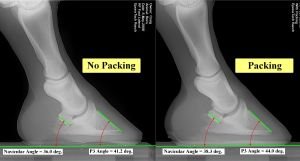

Dále kontroluji, zda má chodidlo dostatek strukturální integrity a dokáže poskytnout adekvátní podporu kopytní kosti. Některá kopyta mají už přirozeně slabé chodidlo a mizernou chodidlovou klenbu. Mizivá klenutost chodidla má vliv na vnitřní uložení kostí. Když se setkám s takovým problémem, snažím se podpořit chodidlo a chodidlovou klenbu použitím flexibilní vyplňovací hmoty (obrázek 8).

Obrázek 8: Přidáním syntetické výplně se mění postavení kopytní kosti. Sledujte rozdíl mezi levým snímkem (bez použití výplně) a pravým snímkem (použita syntetická výplň). Jedná se o rentgenový snímek kopyta na obrázku 2A. Kopyto má dobrou polohu pod osou končetiny, je však vidět, že je kopyto nižší a plošší než by mělo být a je proto vhodné jeho chodidlu poskytnout oporu. >>>

Jinými slovy, chci vytvořit platformu pod kopytem, která pomůže rozložit váhu po celé ploše chodidla. Takový přístup považuji za přínosnější než tradiční model podkování. Tradiční kovové podkovy poskytují jen periferní oporu stěnám.